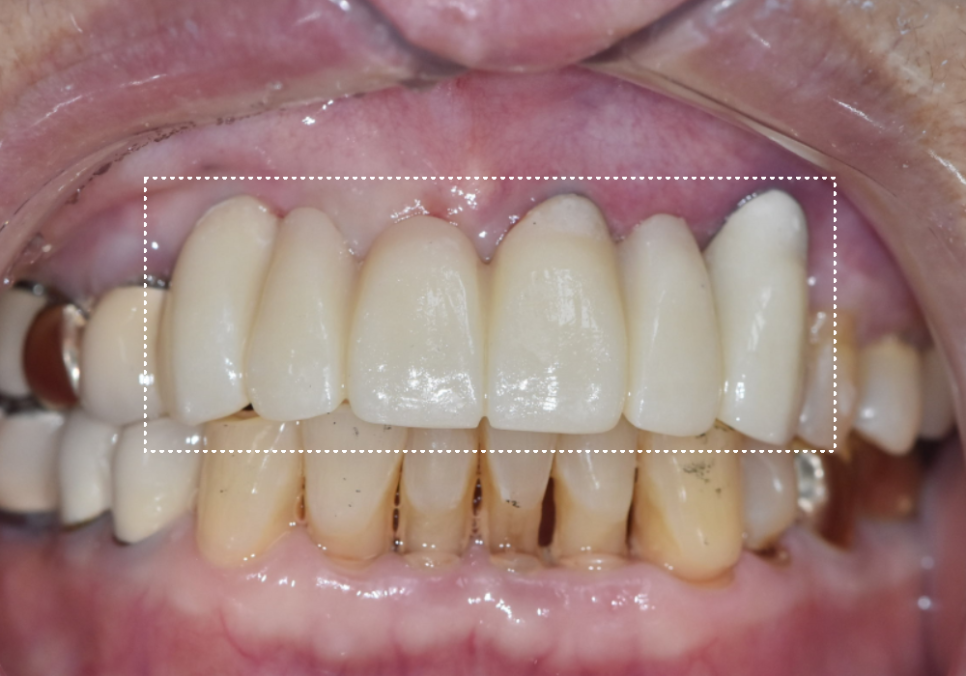

240731

완성된 지르코니아 보철물을 보니

주변 치아와 아주 자연스럽게 어우러지는

만족스러운 결과가 나온 것 같습니다.^^